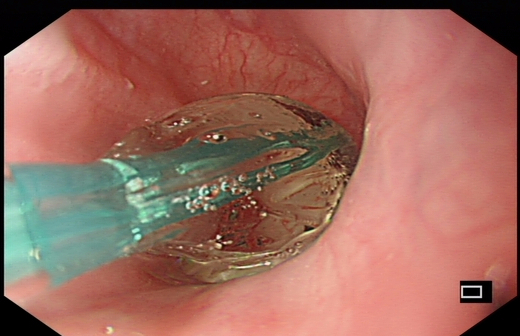

球囊扩张治疗中

X线透视下球囊扩张中